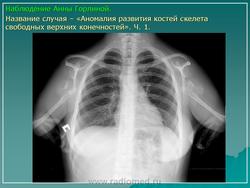

Отсутствие и недоразвитие верхней конечности - тяжелая патология, к счастью она встречается редко. Варианты недоразвития верхних конечностей различные.

Фокомелия или амелия - аномалия развития, при которой верхняя конечность отсутствует полностью, или отсутствует плечо и предплечье, а кисть отходит от недоразвитого плеча и напоминает ласт тюленя. Иногда вместо кисти от недоразвитого плеча отходит только один палец. Такое состояние называется перомелия. Хирургическое лечение такой аномалии малоперспективно. Пациенты обычно хорошо обучаются пользоваться аномальной конечностью. Протезирование выполняется с целью коррекции косметического недостатка.

Эктомелия - полное отсутствие одной или двух конечностей или части конечности. При полном отсутствии конечности проводится протезирование. При частичном - иногда требуется хирургическая коррекция.

Гемимелия - аномалия развития, при которой отсутствует нижняя часть конечности (кисть или кисть и предплечье), а верхние отделы развиты нормально. Лечение заключается в протезировании.